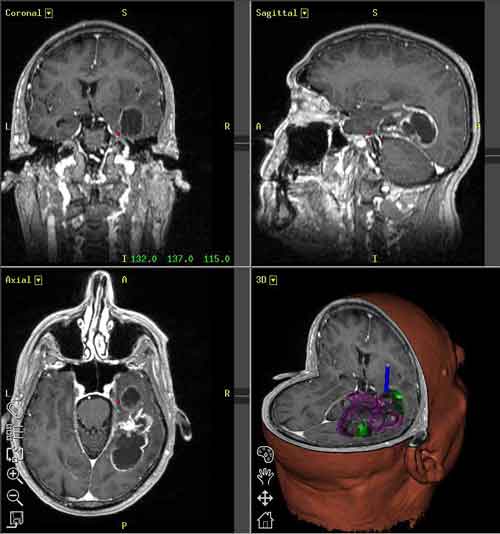

Di tutti i tumori cerebrali, il glioblastoma è il più aggressivo. Ora i ricercatori del Max Delbrück Center for Molecular Medicine (MDC) di Berlin-Buch, in Germania, hanno dimostrato in che modo la sua crescita viene controllata dalle cellule staminali presenti nel cervello e dai loro precursori.

I glioblastoma è anche il tumore più comune tra soggetti adulti, in particolare nella quinta e sesta decade di vita. Le sue cause sono in gran parte sconosciute, ma si ipotizza che qualche fattore induca le cellule staminali neurali o i loro precursori a mutare, diventando cellule tumorali.